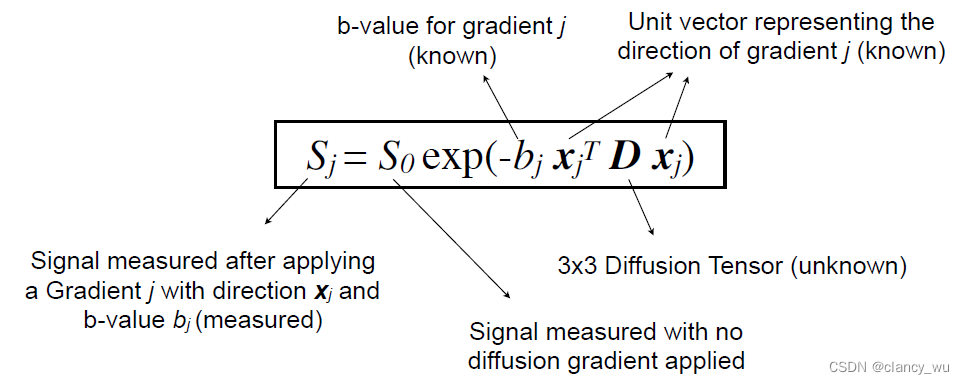

DTI的原理基础是弥散张量模型,Diffusion Tensor Model。即在每一个体素里计算它的

S

j

S_j

Sj

在计算的时候,是按照定义的坐标系进行计算,XYZ坐标系:

其实还需要计算它的解剖学坐标系:

这样,通过这些定义的坐标系,我们就能用公式来表达各向异性和各向同性: